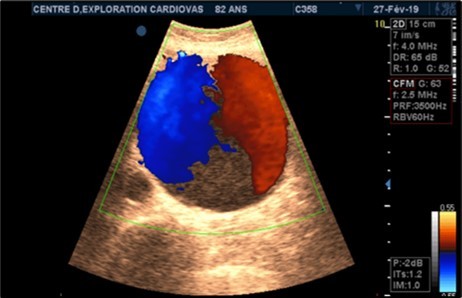

Aneurysms were thrombosed in 24 patients (75%). (Figure 3) and (Figure 4) Arterial occlusion was found in 11 patients (73.33%) and significant stenosis in 4 patients (36.36%). (Table 7).

Figure 3.Large fusiform subrenal abdominal aortic aneurysm of 9.28cm thrombosed at 4/5 in an 82-year-old woman (CEC ‘Saint-Esprit’ from AMP-MCV).

Figure 4.Large fusiform subrenal abdominal aortic aneurysm of 9.28cm thrombosed at 4/5 in an 82-year-old woman (CEC ‘Saint-Esprit’ from AMP-MCV).